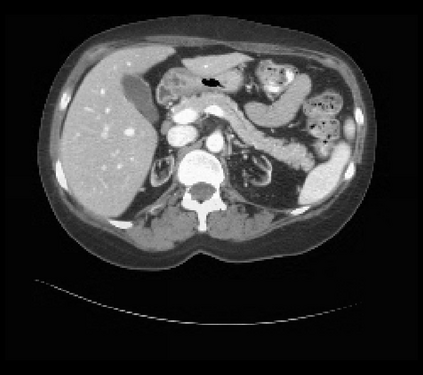

It is imperative to ensure the robustness of deep learning models in critical applications such as, healthcare. While recent advances in deep learning have improved the performance of volumetric medical image segmentation models, these models cannot be deployed for real-world applications immediately due to their vulnerability to adversarial attacks. We present a 3D frequency domain adversarial attack for volumetric medical image segmentation models and demonstrate its advantages over conventional input or voxel domain attacks. Using our proposed attack, we introduce a novel frequency domain adversarial training approach for optimizing a robust model against voxel and frequency domain attacks. Moreover, we propose frequency consistency loss to regulate our frequency domain adversarial training that achieves a better tradeoff between model's performance on clean and adversarial samples. Code is publicly available at https://github.com/asif-hanif/vafa.